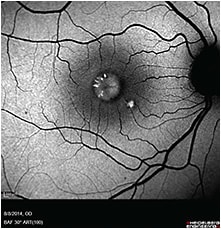

As fast as my career was developing, so were the technological advancements in imaging. Film photography transitioned to digital photography, which provided instant results versus waiting for film to develop. Digital imaging added a new angiographic test, indocyanine green (ICG), to study the choroid and its vessel flow. Digital imaging advanced through another important tool, optical coherence tomography (OCT). A quick and noninvasive way to look at the retinal layers, OCT obtains high-resolution cross-sectional images versus the retinal levels that photography showed. It didn’t take long for OCT technology to evolve into higher resolution and faster capture time using spectral domain.

The recent technology using confocal scanning laser ophthalmoscopy (cSLO) in ophthalmic imaging has made it quicker and easier to capture needed images on patients. Camera systems have broadened our view from lower angles to ultra-widefield imaging that captures 133° to 200° of the retina in one image. The ultra-widefield camera systems have increased in use throughout practices and universities to better study the peripheral retina and management of peripheral diseases for patient care.

Increasing in popularity with clinic and research settings is fundus autofluorescence, which uses cSLO to map fluorophores in inherited retinal diseases and geographic atrophy. OCT angiography (OCT-A) is one of the newest additions to imaging modalities. OCT-A technology uses light reflectance of the surface of moving red blood cells to highlight the different layers of vessels. This lessens the use for intravascular dyes, such as fluorescein and ICG, making a noninvasive approach for the patient.